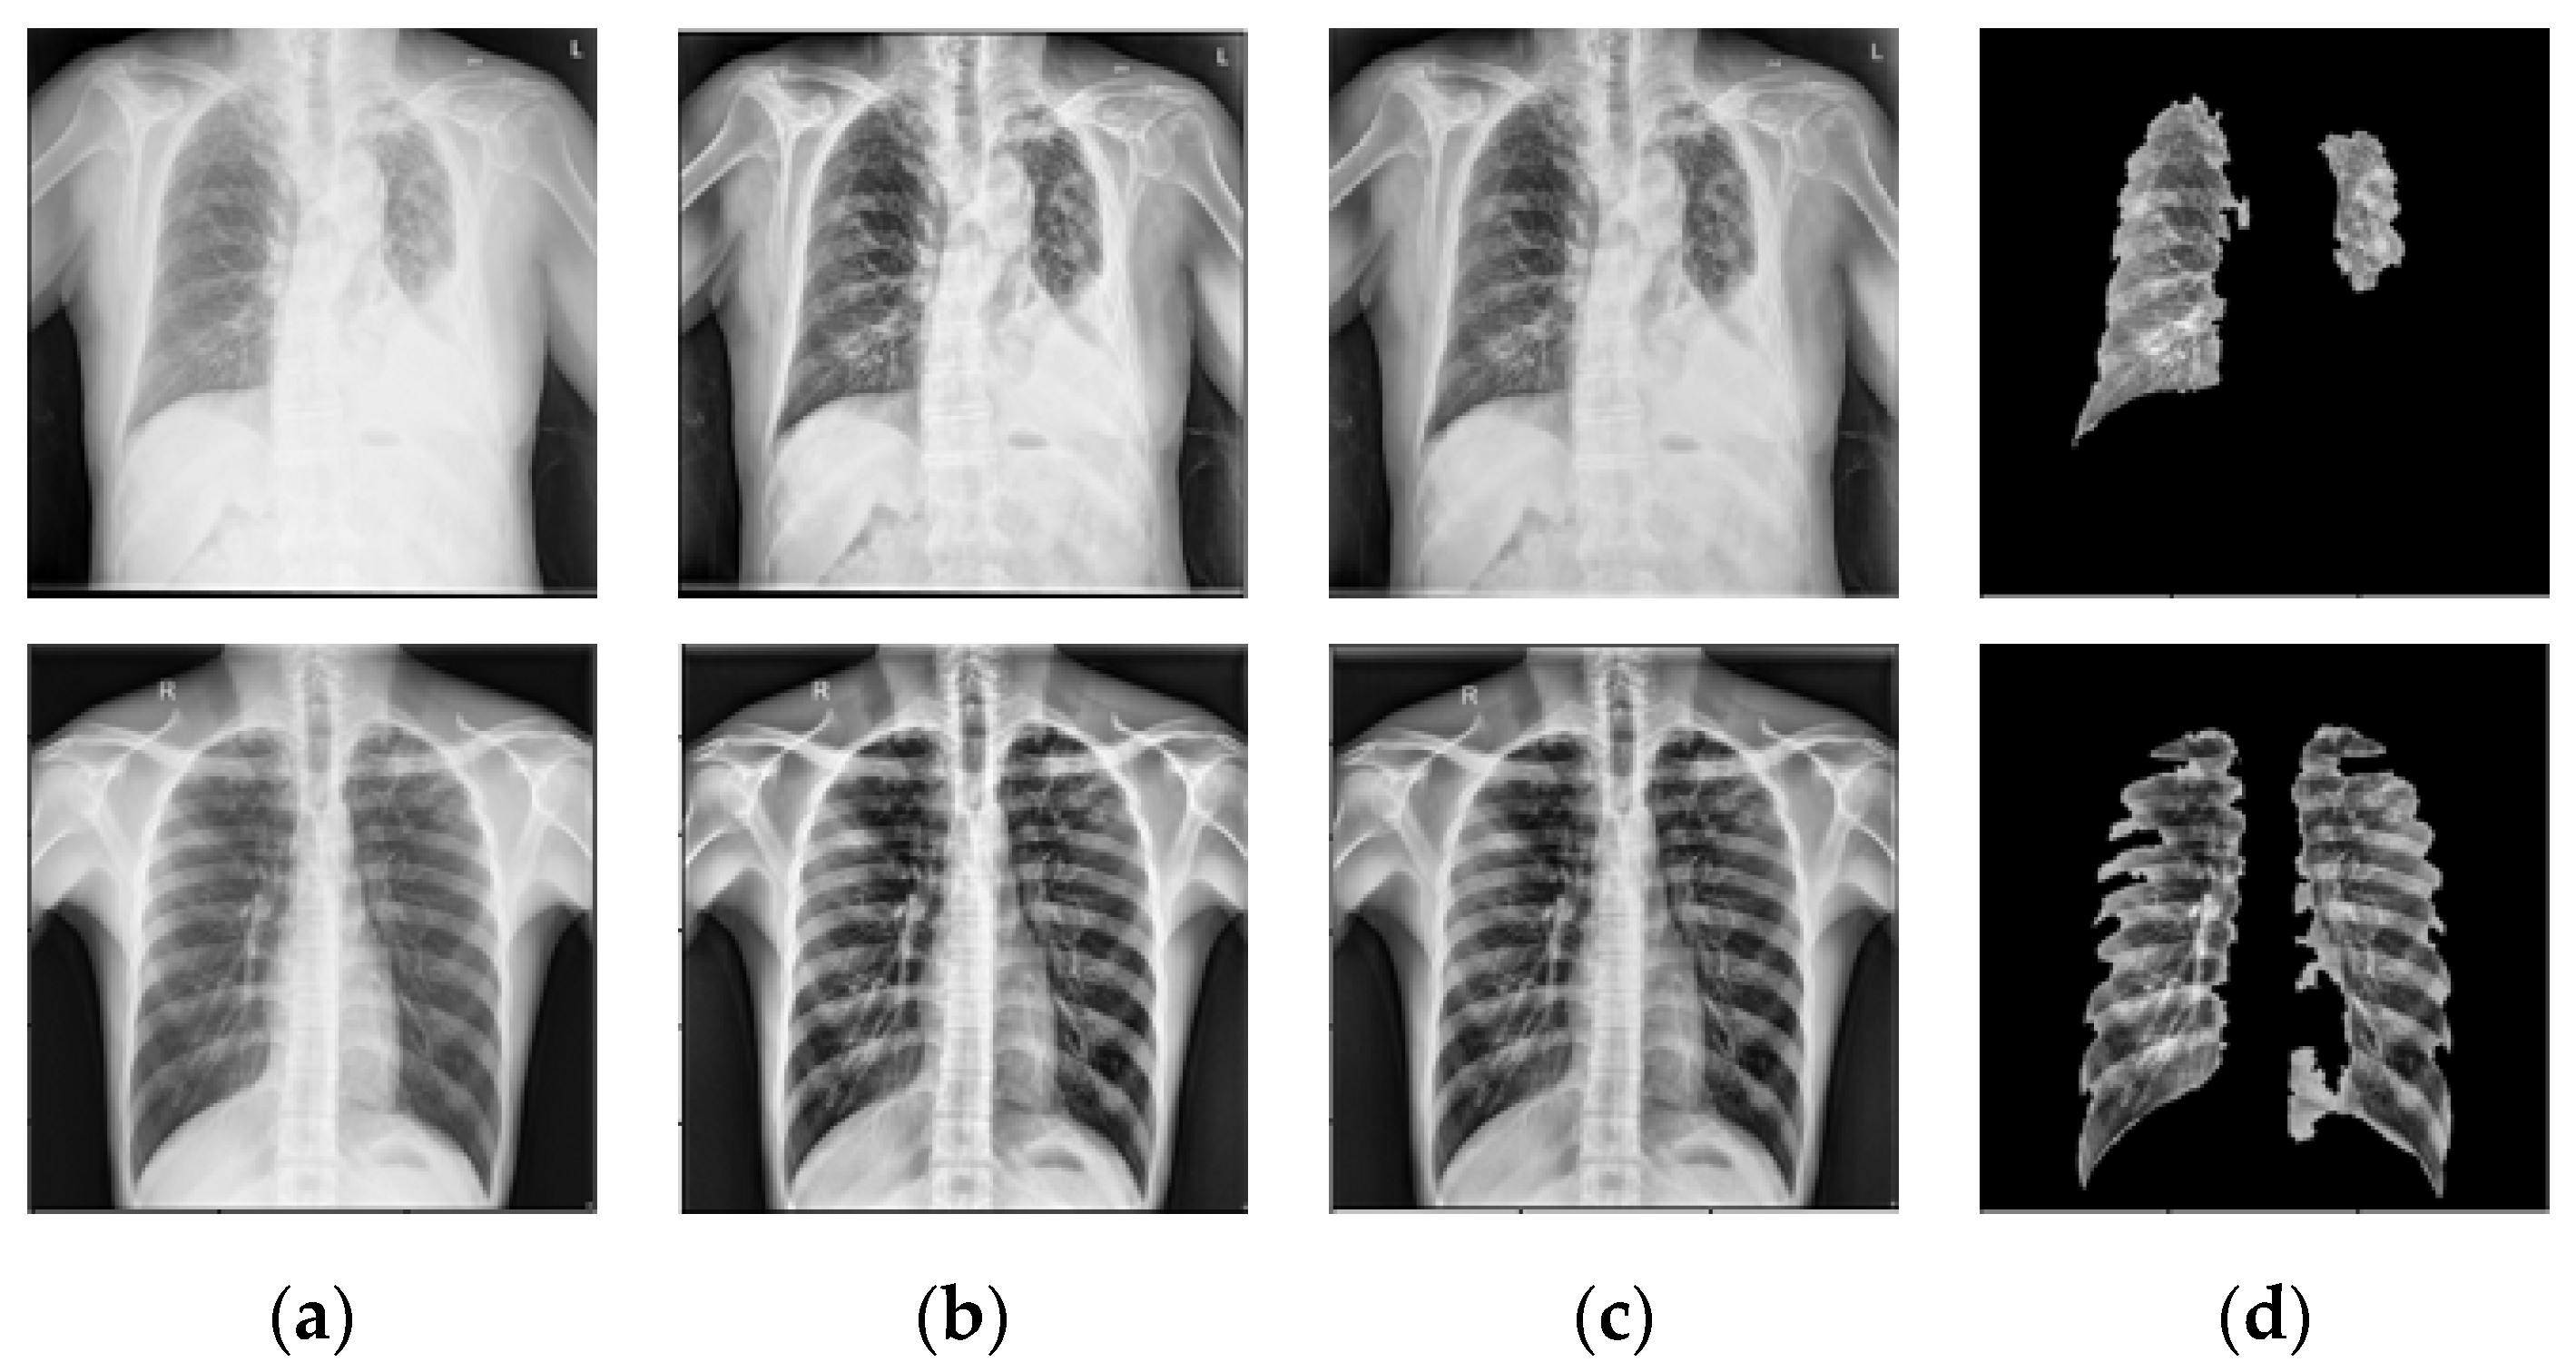

- NLM (National Library of Medicine) dataset [16,20,21]: This was made by two publicly accessible datasets including the Montgomery County CXR set (MC) and Shenzhen (CHN) dataset. The MC dataset was compiled in collaboration with Montgomery County, Maryland, the United States’ Department of Health and Human Services. The collection includes 138 frontal CXRs from Montgomery County’s tuberculosis screening program, where 80 CXRs were normal cases while 58 CXRs had TB manifestations. The X-rays were taken with a Eureka stationary X-ray machine (CR) and provided as 12-bit gray level images in portable network graphics (PNG) format. Moreover, the Digital Imaging and Communications in Medicine (DICOM) format is also available upon request. The X-rays were either 4020 × 4892 or 4892 × 4020 pixels in size. The Shenzhen dataset was collected in collaboration with Shenzhen No. 3 People’s Hospital, Guangdong Medical College, Shenzhen, China. The CXRs were from outpatient clinics and captured as part of the daily hospital routine within a 1-month period, mostly in September 2012, using a Philips DR Digital Diagnost system. The dataset contained 662 frontal CXRs, of which 326 belonged to normal cases while 336 had TB manifestations including pediatric X-rays (AP). The X-rays are provided in PNG format, and can vary in size, but is approximately 3 K × 3 K pixels.

- Belarus dataset [20]: The National Institute of Allergy and Infectious Diseases, Ministry of Health, Republic of Belarus, collected the Belarus Set for a drug resistance study. There are 306 CXRs in the dataset, representing 169 patients. The Kodak Point-of-Care 260 system was used to take chest radiographs with a resolution of 2248 × 2248 pixels. All images in this database had been infected with tuberculosis.

- RSNA dataset [20]: The RSNA pneumonia detection challenge dataset contains approximately 30,000 chest X-ray images, 10,000 of which were normal and the rest were abnormal as well as the lung opacity images. The DICOM format was used for all images. A total of 3094 normal images were taken from this database and the remaining 406 normal images were taken from the NLM database to create a normal database of 3500 chest X-ray images for this study.